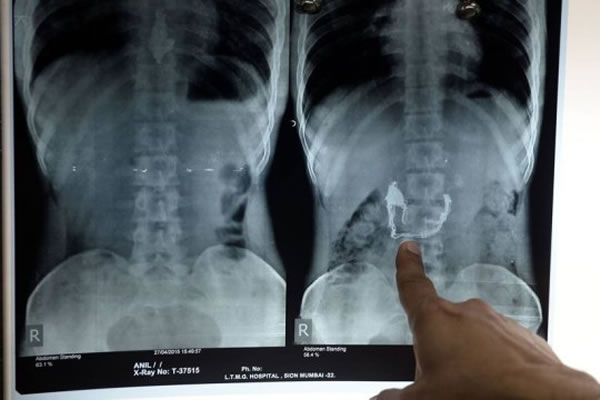

Um indiano foi acusado de roubar um colar de ouro de uma dona de casa e engolir a joia para apagar as provas, nesta sexta-feira, em Mumbai. Anil Jadhav foi detido pela polícia e levado ao hospital Lokmanya Tilak. Um raio-X mostrou o cordão e um pingente alojados no estômago do criminoso. Jadhav foi alimentado com líquidos especiais e mais de 60 bananas até expelir a jóia - avaliada em US$ 1 mil, cerca de R$ 3 mil - pela fezes. Agora, os médicos tratam quatro edemas internos provocados pelo colar.